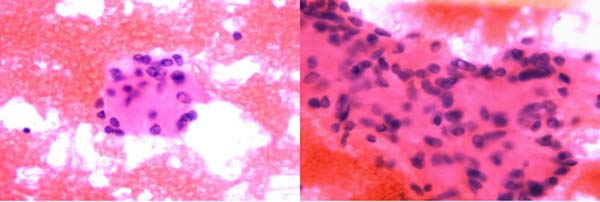

甲状腺-FNA:可见较多量甲状腺滤泡上皮细胞,排列松散或小团状,细胞核增大、拉长,核沟和核内假包涵体易见,背景中可见均质粉染透明变物质。

HTT通常表现为单侧单发有包膜的结节,界限清楚,切面实性、分叶状,灰白至淡黄色。镜下肿瘤以形成小梁状优势结构为特征,或呈实性巢状、腺泡状结构,间质富于窦状毛细血管;肿瘤细胞梭形或呈多角形,胞质丰富,嗜酸或透明,长轴垂直于基底膜,核的特征类似于PTC,核沟及核内假包涵体易见,核周可见特异性黄色小体,核分裂象罕见。瘤细胞巢间可见大量透明变的基底膜样物质沉积,PAS染色及胶原Ⅳ免疫组化染色阳性。HTT细胞核的特征与PTC有重叠,针吸细胞学易误诊为PTC,HTT细胞学示甲状腺滤泡上皮细胞丰富,围绕淀粉样透明变基质呈放射状排列,无乳头及滤泡结构,无平铺细胞片,细胞核拉长呈梭形,核膜不规则,核沟及核内假包涵体易见,胞界不清。Marina N. Nikiforova等研究表明,与PTC不同,GLIS重排在HTT中较普遍,特别是PAX8–GLIS3重排,这种融合基因导致GLIS过表达,进一步上调细胞外基质基因引起胶原沉积,从而产生镜下肿瘤组织中胶原丰富的现象。